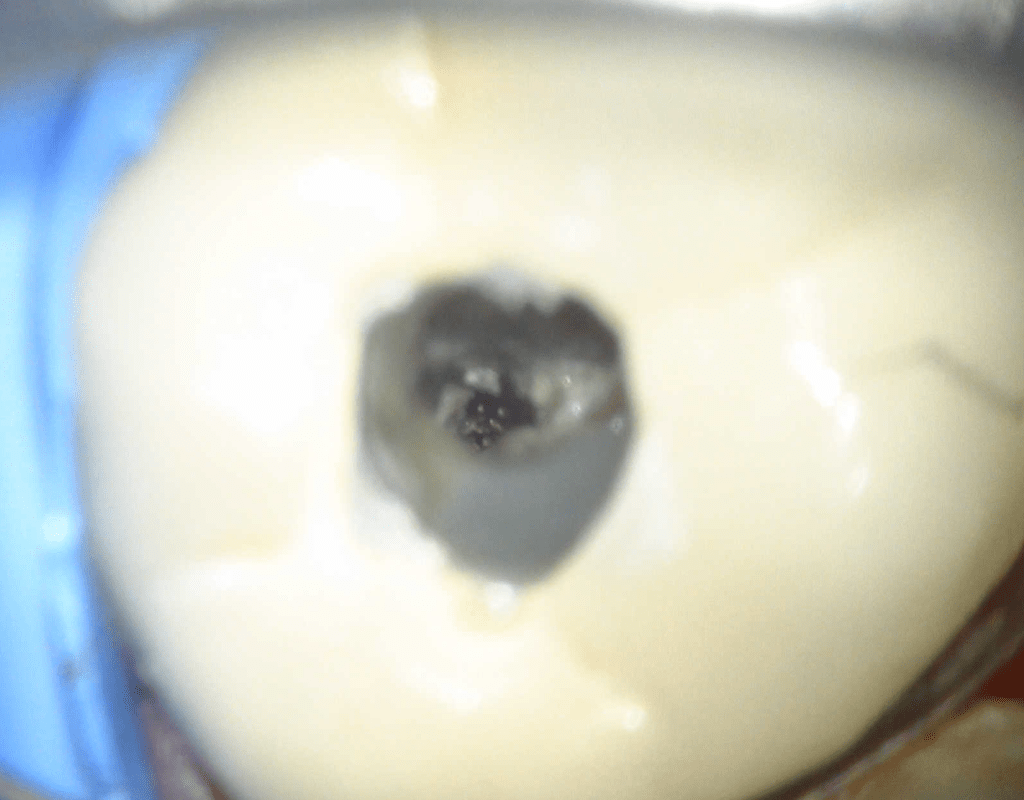

Diagnóstico de fisuras y fracturas

Fisura, remoción amalgama para explorar

Acceso ultraconservador a través de incrustación reciente